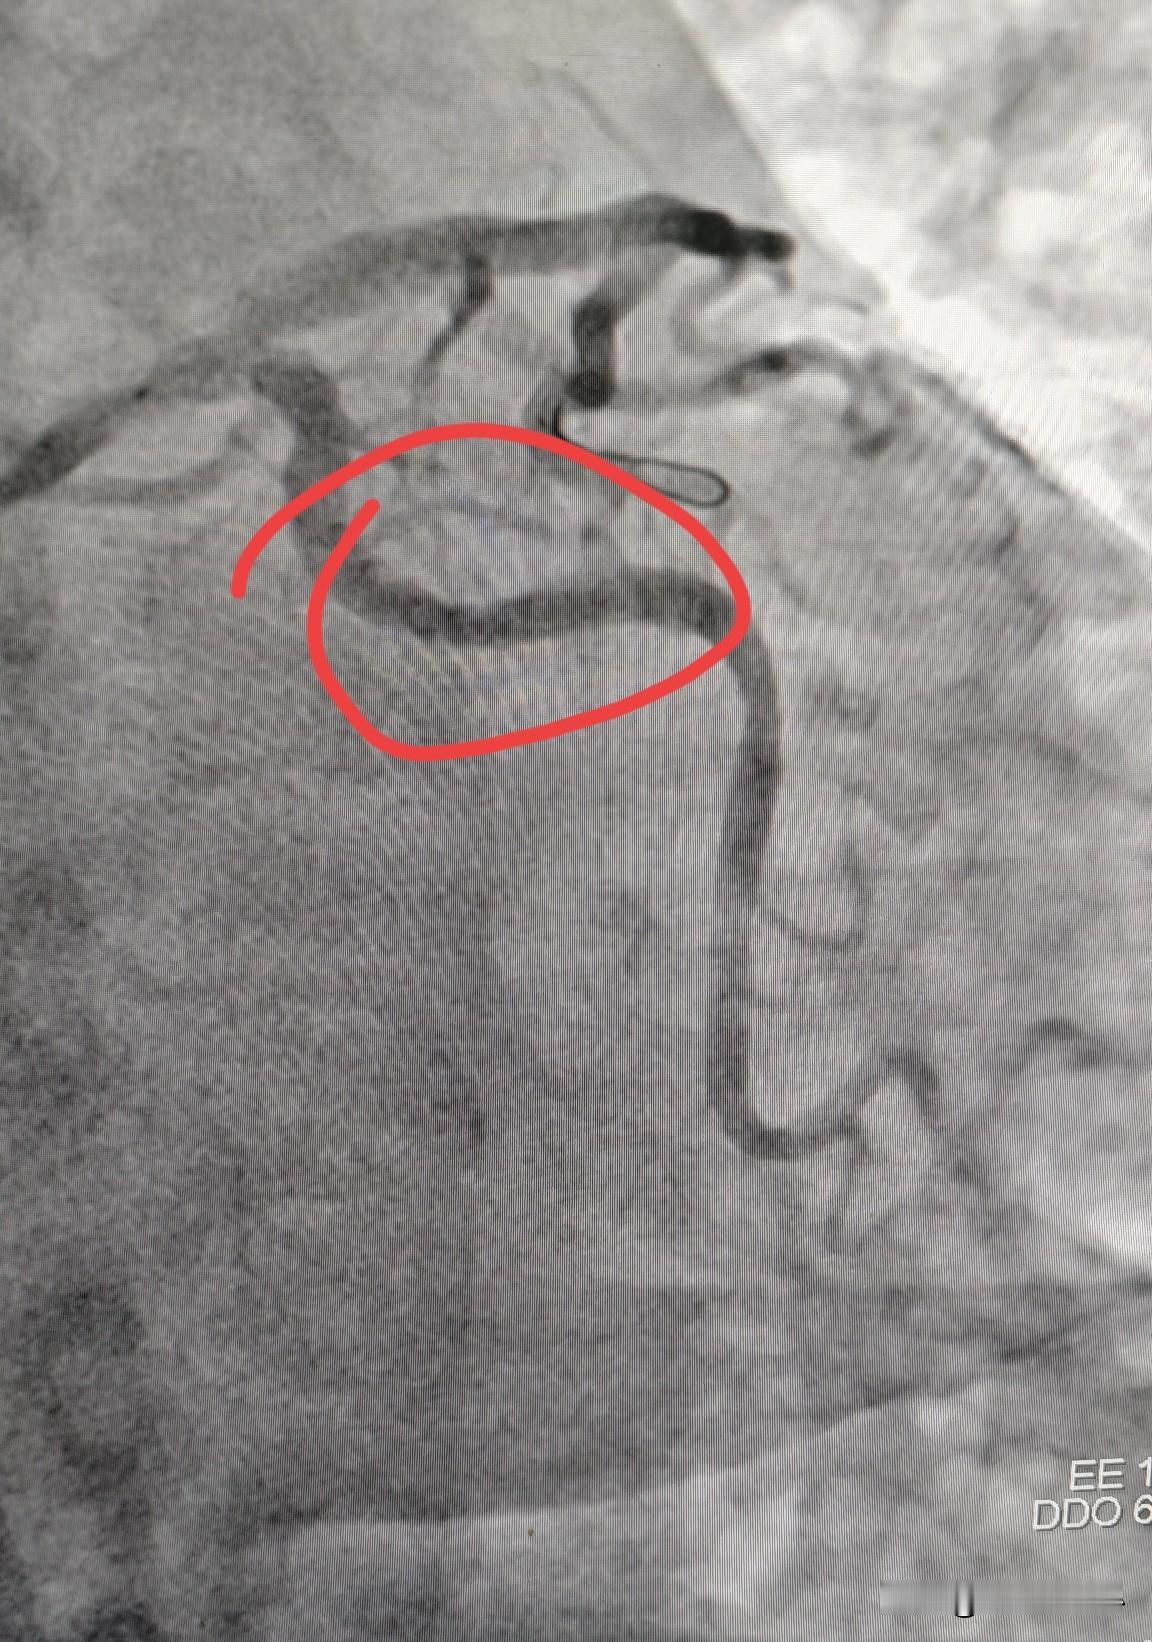

冠状动脉痉挛什么样?快来直观看一下冠状动脉痉挛。 这是一个做冠脉支架的患者,在导丝通过回旋支时,原本没有病变的回旋支出现了一个充盈缺损,类似于动脉斑块的表现(图1)。在冠脉内注射硝酸甘油以后,再次造影,发现充盈缺损消失,狭窄解除(图2)。 这就是在导丝的刺激下,原本没有病变的血管因为痉挛收缩了,从而形成一个血管狭窄的假象。但这种狭窄在使用硝酸甘油等扩血管药物后就会解除。 临床上有一种心绞痛,就叫变异性心绞痛,就是冠状动脉痉挛引起的。这种冠状动脉痉挛一般在使用硝酸异山梨酯或者是盐酸地尔硫卓以后,冠状动脉痉挛就可以得到控制,心绞痛的症状就可以得到缓解。冠心病 冠动脉狭窄